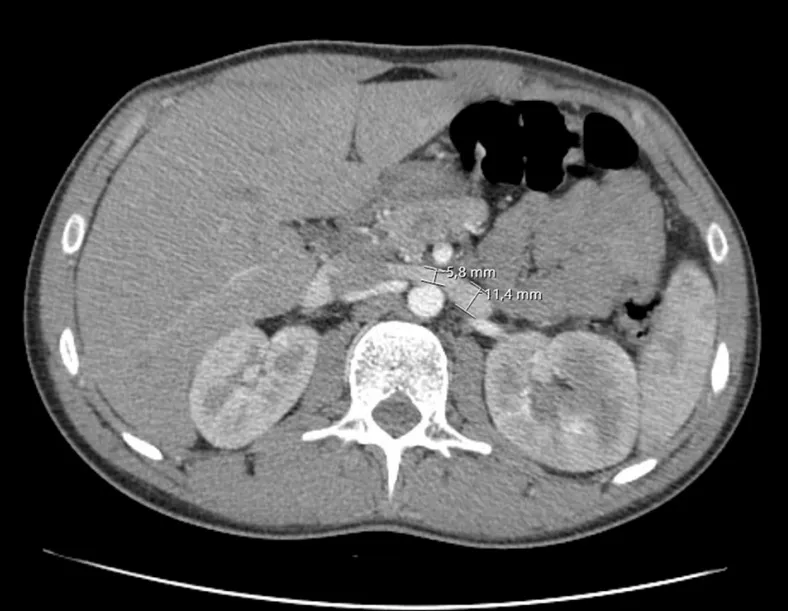

DRC indeterminada ou você esqueceu de fazer o básico? Veja tudo aqui

DRC “indeterminada” raramente é falta de diagnóstico — quase sempre é falta de método. Tempo de evolução, urina bem avaliada, USG renal e história clínica dirigida mudam conduta e evitam erros comuns na prática nefrológica.